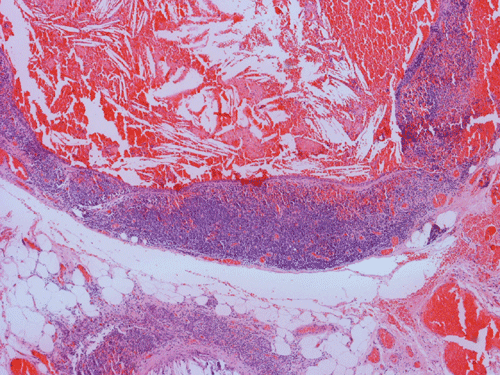

Histopathology: The lesion is encapulated cystic structure with the wall lined by nodules of lymphoid tissue (Panel A  and B) that are devoid of any evidence of hematopoiecic malignancy. Within this lymphoid tissue are small pink islands (Arrow in Panel C) and on higher magnification (Panel D) these islands are squamous cell nests. These islands are Hassell corpuscles and the lymphoid tissue is in fact thymic tissue. The cyst appears to have sustained repeated hemorrages. Both recent hemorrhage (Panel E) and cholesterol clefts consistent with resolved hemorrhage (Panel F) are present.